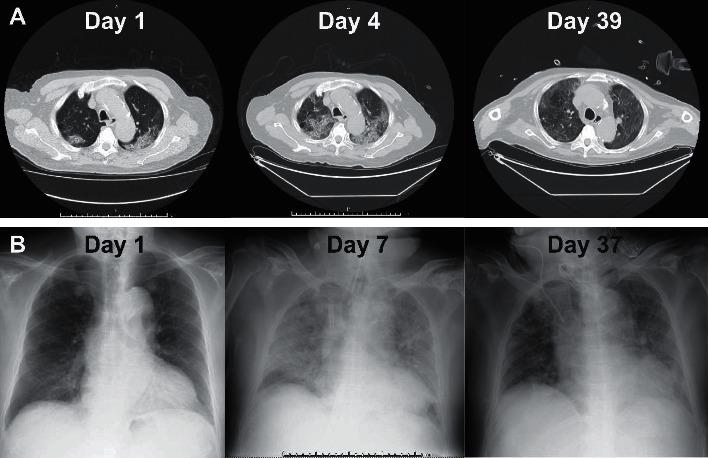

Although a variety of existing drugs are being tested for patients with coronavirus disease 2019 (COVID-19), no efficacious treatment has been found so far, particularly for severe cases. We report successful recovery in an elderly patient with severe pneumonia requiring mechanical ventilation and extracorporeal membrane oxygenation (ECMO). Despite administration of multiple antiviral drugs, including lopinavir/ritonavir, chloroquine, and favipiravir, the patient's condition did not improve. However, after administration of another antiviral drug, remdesivir, we were able to terminate invasive interventions, including ECMO, and subsequently obtained negative polymerase chain reaction results. Although further validation is needed, remdesivir might be effective in treating COVID-19.